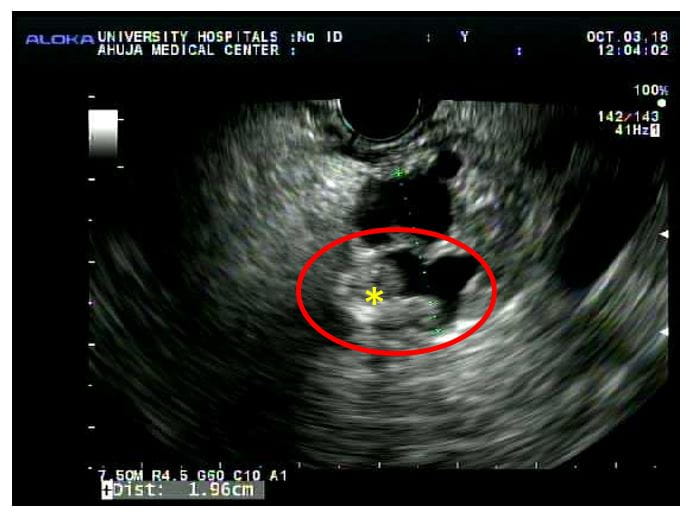

- If the cyst is less than 2 cm, an MRI at six months and then annually until they're no longer a surgical candidate

- If the cyst is greater than or equal to 2 cm, MRIs every six months for one year, then once annually until they're no longer a surgical candidate

Pancreatic cysts are saclike pockets of fluid on the pancreas. Serous cysts are filled with thin fluid and are usually benign. Some subtypes of mucinous cysts, which are filled with a thicker fluid, are more concerning.